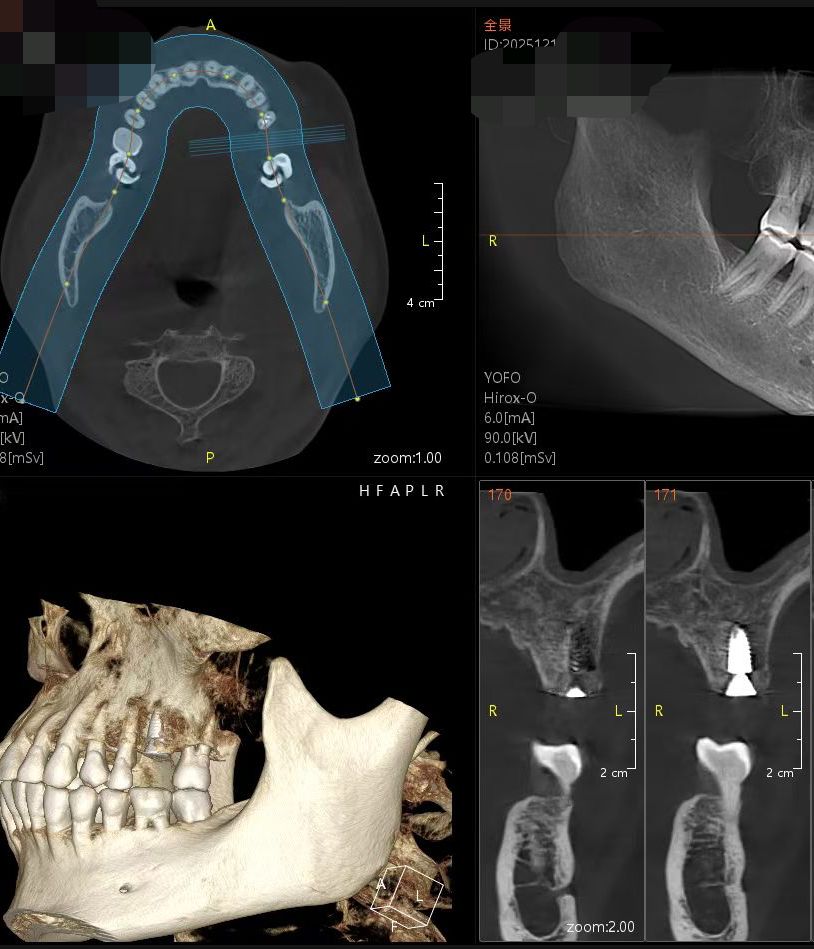

3D Guided Implant Surgery

Aiyi Dental utilizes state-of-the-art equipment to ensure your surgery is safe, fast, and precise. By combining CBCT (3D Scans) with full-digital oral scanning, we create a customized "Surgical Guide" tailored to your unique anatomy.

Think of this guide like a GPS navigation system for your procedure. It offers three major advantages over traditional surgery:

1. Pinpoint Accuracy (Safety)

The digital guide strictly controls the angle, position, and depth of the implant. This eliminates guesswork and significantly minimizes the risk of human error, ensuring a perfect fit.